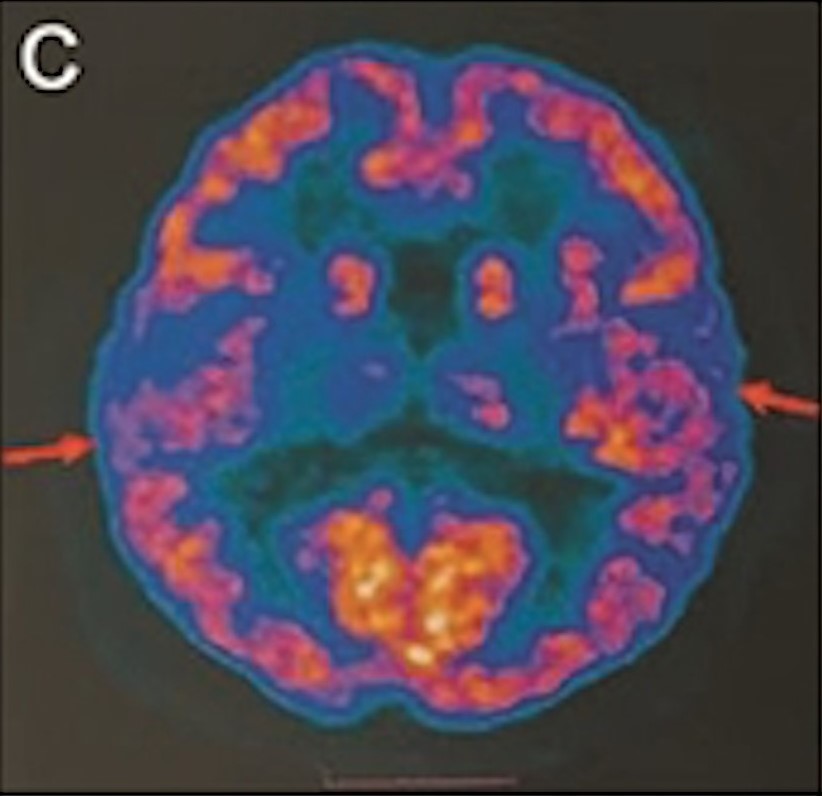

最年輕的19歲阿茲海默癥男子腦部掃描結(jié)果:

▲19歲阿茲海默癥(認知障礙癥/腦退化癥)男子腦部掃描結(jié)果。北京青年報

該名19歲男子到醫(yī)院接受多項檢查,包括腦脊液指標檢測及正電子掃描。結(jié)果顯示,他出現(xiàn)輕度腦萎縮等癥狀,最終被臨床診斷為“阿茲海默癥”。